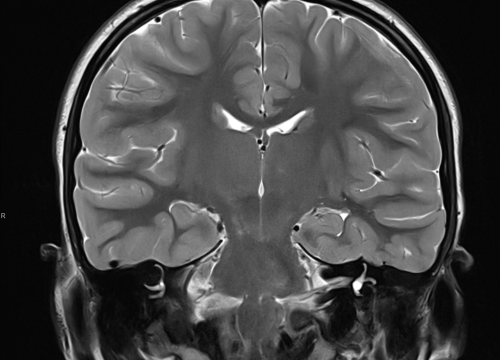

Ako su vam potrebni specijalistički pregledi mamografija, RTG, UZV, CT i MR, koji se inače koriste za dijagnostiku velikog broja zdravstvenih problema, možete ih obaviti već danas ili sutra.